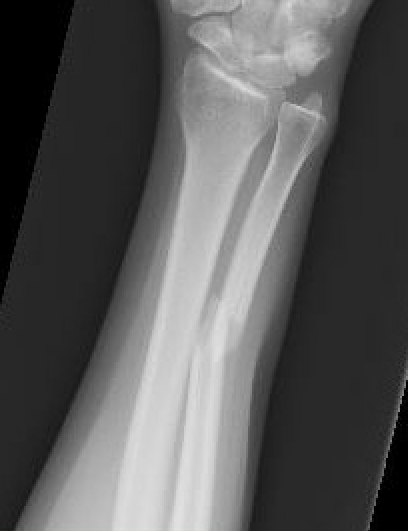

Nonoperative management

Indications

Minimally displaced fractures

- < 50% displaced

- < 10 degrees angulation